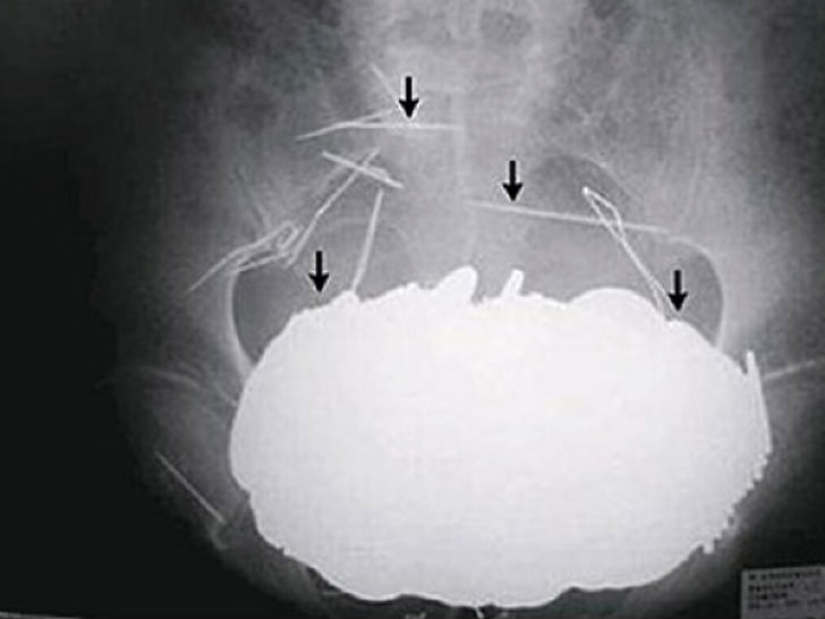

Yes, swallowing silverware is an expensive pleasure. What about the 78 silver spoons that a 52-year-old woman swallowed in the Netherlands?